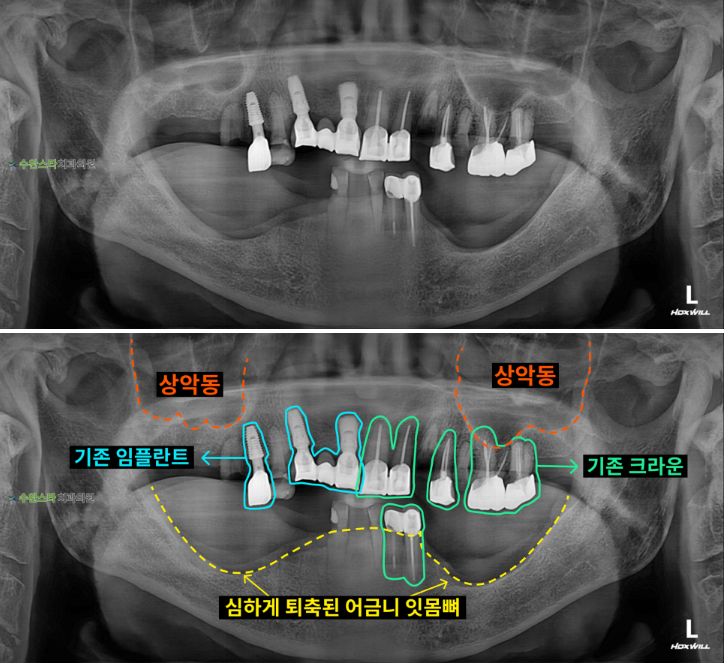

내원 시 파노라마

처음 내원 시 파노라마, 80대 남성 (2025.10 촬영)

내원 시 파노라마 사진입니다.

상악은 타 치과에서 식립한

임플란트와 크라운입니다.

하악의 어금니 쪽 잇몸뼈가

많이 녹고 퇴축되어 있는

모습입니다.